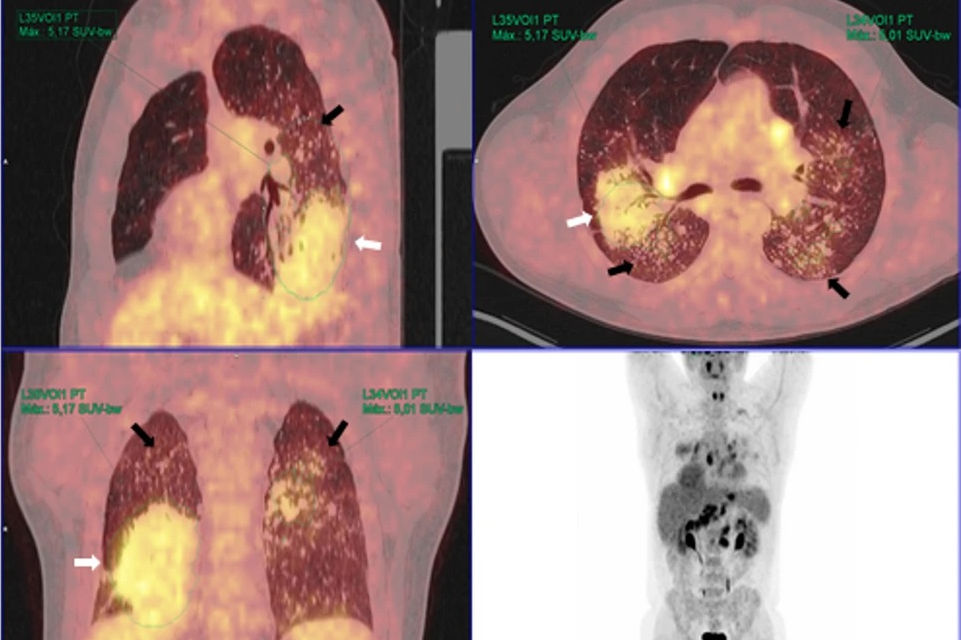

Contrast-enhanced chest CT shows upper predominant fibrosis/lung scarring (red oval), solid masses adjacent to a left-sided pneumothorax (yellow oval) and diffuse silicotic nodules (purple circle). This patient had a history of working in the countertop-cutting industry (15 years), smoking cigarettes (10 pack years), and active tuberculosis (treated 7 years prior and excluded at the time of this image with laboratory testing). Image courtesy of the RSNA.

The team classified CT images as typical or atypical for chronic silicosis. Markers for atypical findings included mediastinal lymphadenopathy and upper-lobe predominant small nodularity and/or progressive massive fibrosis. All 21 patients were symptomatic, with the most common symptoms being dyspnea (n = 19) and cough (n = 17).

On secondary retrospective review, the team found that 11 cases were typical for silicosis, while the other 10 cases had atypical imaging features. Pulmonary function tests meanwhile showed a restrictive pattern in 18 cases.